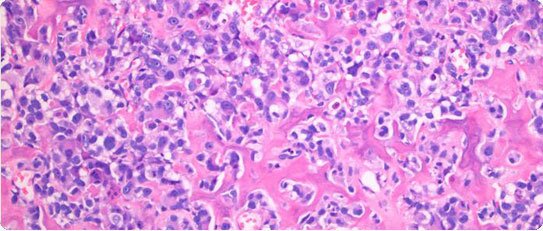

Specialist diagnostic histopathology is provided by a team of dedicated bone and soft tissue tumour pathologists, and also includes molecular genetics to identify characteristic chromosomal translocations and gene mutations (abnormalities of the genetic material at the centre of the tumour cell), now an essential component of a state-of-the-art diagnostic service.